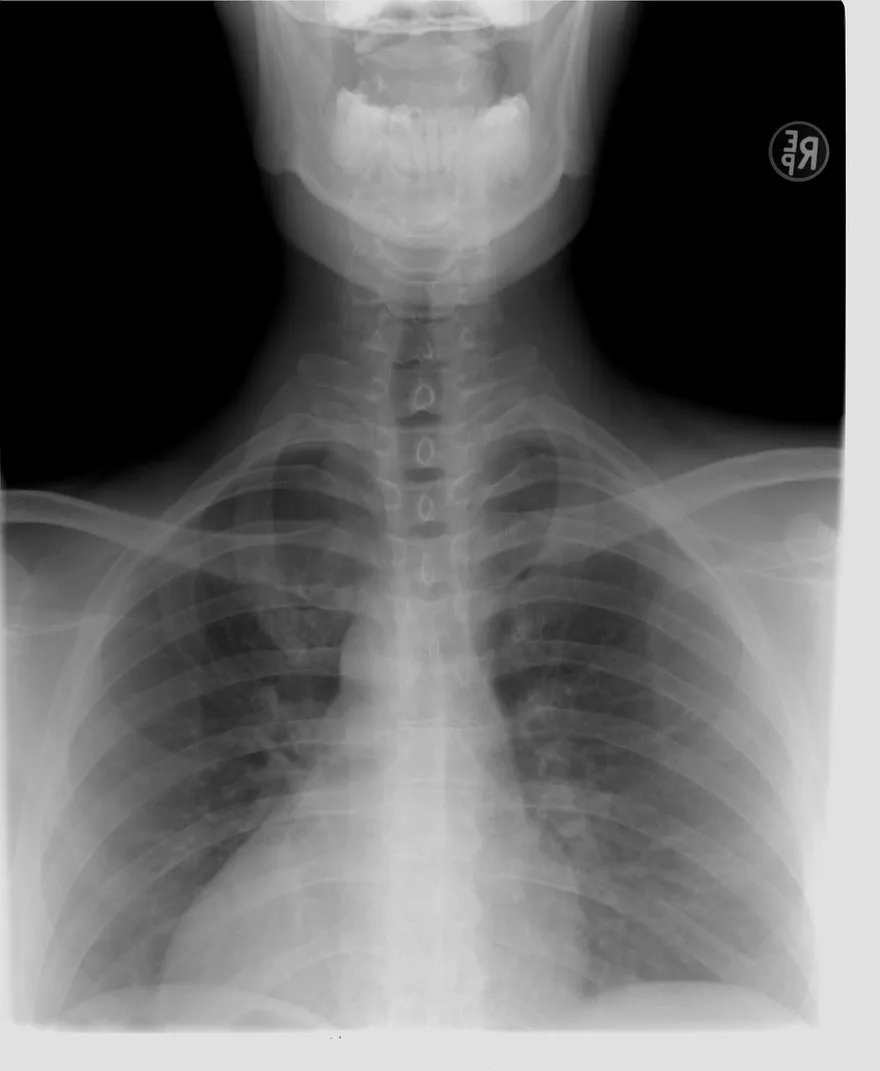

55歲女大腿痛竟是肺癌4期 激動喊:上週X光正常!醫揭原因

X光

肺癌

腫瘤轉移